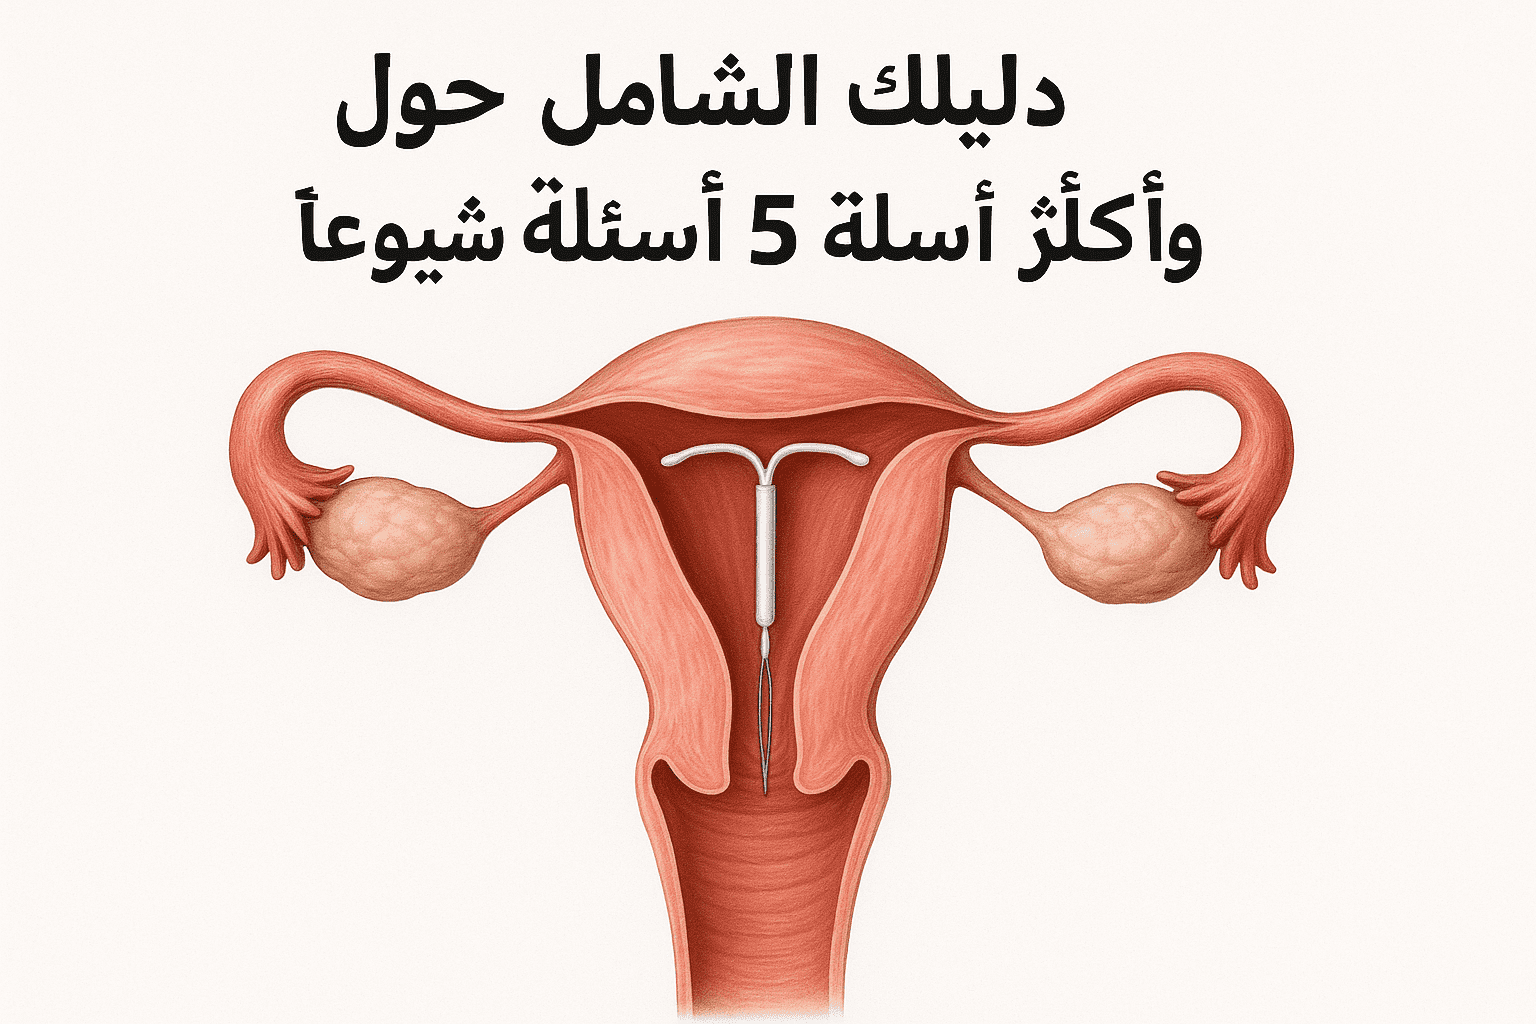

مقالات طبية من مساهمات الأطباء